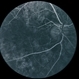

- Imaging device

Fundus camera

Optos Tx-200

- Fluorescein angiography montage of the right eye of a 56-year-old male with Bietti's crystalline dystrophy demonstrating advanced chorioretinal atrophy.